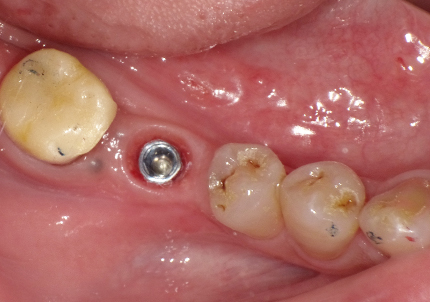

患者:S.G様(55歳/男性)

初診日 :2014年6月10日

主訴 :義歯が嫌いで使わず奥歯が咬めないので、全体の治療を希望する

治療計画 :

・上顎補綴物再製

・右下2本インプラント

・左下ジルコニアクラウンブリッジ

1.初診時口腔内写真(2014年6月)

5.インプラント埋入(2021年6月)

※ 初期固定35N/cm確認する